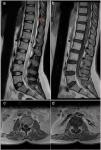

Presentamos el caso de una mujer de 31 años remitida a nuestro departamento con una paraparesia asimétrica progresiva de 10 meses de evolución y disfunción vesical ocasional. Con el diagnóstico de malformación arteriovenosa espinal de tipo IV, se realizó una embolización programada tras la que se produjo una hemorragia subaracnoidea masiva debido a la laceración de la arteria espinal anterior que precisó una craniectomía bifrontal urgente. Discutimos el papel del neurocirujano en el tratamiento de las complicaciones derivadas del tratamiento endovascular de la patología espinal.

We reported a 31 years old female referred to our department with progressive asymmetric spastic paraparesia for 10 months of evolution and occasional bladder dysfunction. With the diagnosis of a type IV arteriovenous malformation, a scheduled embolization was performed resulting in a massive subarachnoid hemorrhage due to the ASA laceration requiring an emergency bifrontal craniectomy. We discuss the neurosurgeońs role in complications during endovascular spinal vascular pathology treatment.